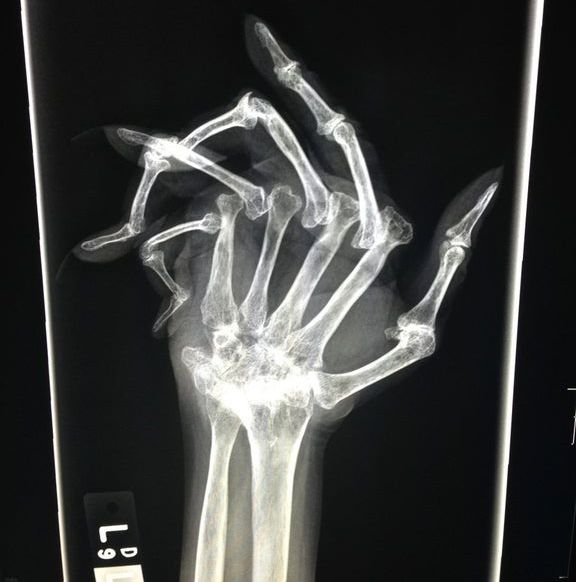

Desde su descubrimiento en 1895 por parte del profesor alemán Wilhelm Röntgen los rayos X han jugado un papel fundamental en las sociedades humanas. Son usados en campos tan distintos como el sanitario, la seguridad en el transporte e incluso la identificación de obras de arte. Su utilización está tan extendida que a veces deja imágenes tan curiosas como las recogidas en esta galería.